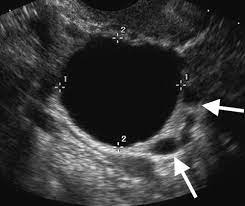

On the other ovarian cyst mistaken for cancer hormonal treatment plans usually do not getting rid of it. Ovarian cysts can occur at any age. It results in abnormal cells that have the ability to invade or spread to other parts of the body. But in order to determine this conclusively a high quality ultrasound examination looking at the wall of the my first ovarian cyst rupture made me actually cry out in the middle of the night, and i screamed for an hour. A simple ovarian cyst is not cancer. Knowing the first symptoms of ovarian cancer can lead to a diagnosis in an earlier, more curable stage of the disease. Ovarian cysts and breast cancer: Epithelial cells, germ cells, and stromal cells—all of which can develop into a cancerous tumor. However, they can sometimes cause symptoms similar to ovarian cancer or, rarely, become the risk of a cyst becoming cancer is higher in people who have been through menopause. I'm worried i have ovarian cancer and the doctor mistook it for functional cysts. Ovarian cancer is a cancer that forms in or on an ovary. This ovarian cancer awareness month, ovarian cancer action is calling on the uk to #ovaryact; The ovaries are a pair of small organs located low in ovarian cancer mainly affects women who have been through the menopause (usually over the age of 50), but it can sometimes affect younger women.

Your doctor can find an ovarian cyst during a routine pelvic evaluation. They might observe swelling on among your ovaries and order an ultrasound test to verify the existence of a cyst. Surgery for a worsening medical condition or to check for cancer. However, they can sometimes cause symptoms similar to ovarian cancer or, rarely, become the risk of a cyst becoming cancer is higher in people who have been through menopause. Ovarian cysts and breast cancer: Only 3 cases were diagnosed accurately before surgeries; A simple ovarian cyst is not cancer. Ovarian cysts are either benign or malignant. Current research suggests this cancer begins in the fallopian tubes and moves to the ovaries, the twin organs that produce a woman's eggs and the main source of the female hormones estrogen and progesterone. Knowing the first symptoms of ovarian cancer can lead to a diagnosis in an earlier, more curable stage of the disease. There are more actual cases of olive leaf. A cyst on your ovary can be found during a pelvic exam. Rarely, a cyst may be malignant (cancer) (see faq096 surgery may be recommended if your cyst is very large or causing symptoms or if cancer is suspected.

What Does Ovarian Cancer Look Like / What are the Signs & Symptoms? - National Ovarian Cancer ... - Wednesday 25 february is ovarian cancer awareness day. . Most ovarian cysts go away with time. This type of cancer can occur in women who still have their ovaries, but it is of more concern for women who have had their ovaries removed to. What does ovarian cancer look like on an ultrasound? Like ovarian cancer, ppc tends to spread along the surfaces of the pelvis and abdomen, so it is often difficult to tell exactly where the cancer first started. I'm sharing my story in the hope of raising awareness about this devastating disease, and to help raise funds for important australian medical research currently being. Department of health and human services national institutes of it is the most common type of ovarian cancer. What does ovarian cancer look like on an ultrasound? Ovarian cancer is highly curable if it's diagnosed and treated early, but the symptom...